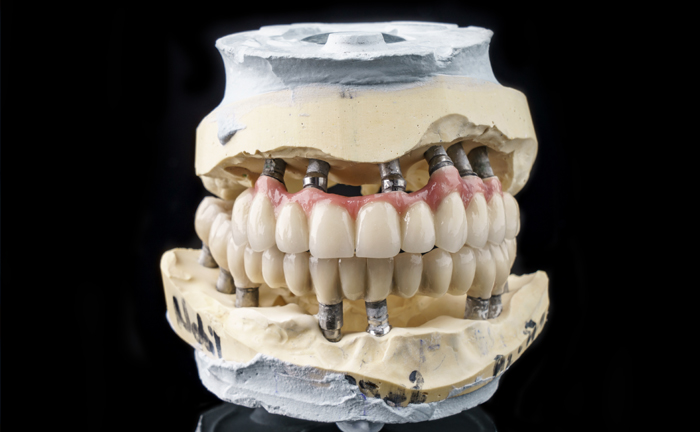

4 dental implants

4 abutments

12 temporary teeth (movable)

12 resin crowns (fixed teeth)

Using the All-On – 4 method; Dental implants are inserted in the same day and in a few hours, a temporary but fixed prosthetic job is performed immediately which will remain until the implants are perfectly integrated into the bone. After about 4-6 months, definitive prosthetic rehabilitation will be performed, which will be screwed onto existing implants. The screw fixing will allow you to remove the restoration (fixed bridge) when necessary.

The specificity of this procedure is that the teeth are fixed on four implants. Thanks to the particular method of inserting the implants, bone reconstruction is not necessary, which is instead a requirement when it is necessary to reconstruct in patients who have total tooth loss.